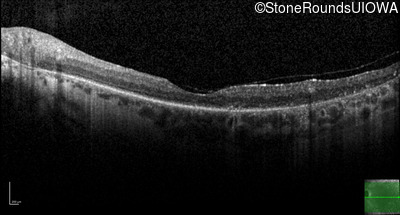

Type 2 Usher Syndrome (IB1b)

Age at visit: 53 years

This 53 year old woman first noticed night blindness at age 18. More recently she has experienced constriction of her visual fields. She has worn hearing aids since childhood.

Diagnosis & molecular findings

Disease Gene Allele 1 variant(s) Allele 2 variant(s) Inheritance mode

Type 2 Usher Syndrome ADGRV1 Arg211 del2ggcAG IVS66-2 A>T AR